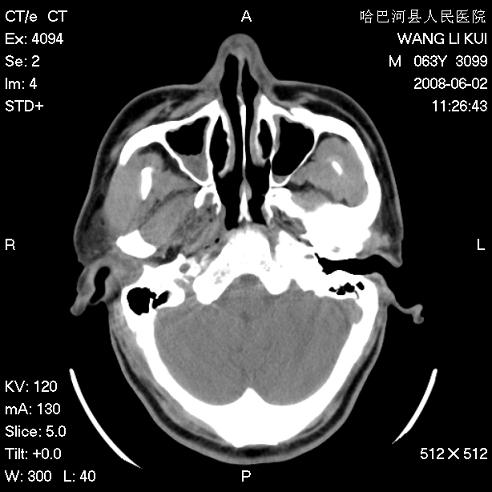

标题: CT13803:反复性鼻塞、流涕一年余 [打印本页]

标题: CT13803:反复性鼻塞、流涕一年余

副鼻窦炎,右上额窦积脓。左眼肌锥内见致密影,视神經受压

1.全组副鼻窦炎2.双侧上颌窦积液

1)全副鼻窦炎(左侧上颌窦黏膜下囊肿或息肉)。2)左眼眶肌锥内不规则小结节状软组织密度影;考虑为小血管瘤可能。建议行ct增强扫描检查。

全组副鼻窦炎,左侧肌锥内不规则形软组织肿块影,与眼外肌密度相当,左侧视神经受压,肿块与视神经及眼外肌分界清晰,眼外肌无增粗,眶壁无破坏,球后脂肪间隙不模糊,考虑良性改变,小血管瘤或神经源性肿瘤可能,建议增强扫描。

谢谢,增强扫描做了,眶内病灶与海绵窦同步明显强化,血管瘤